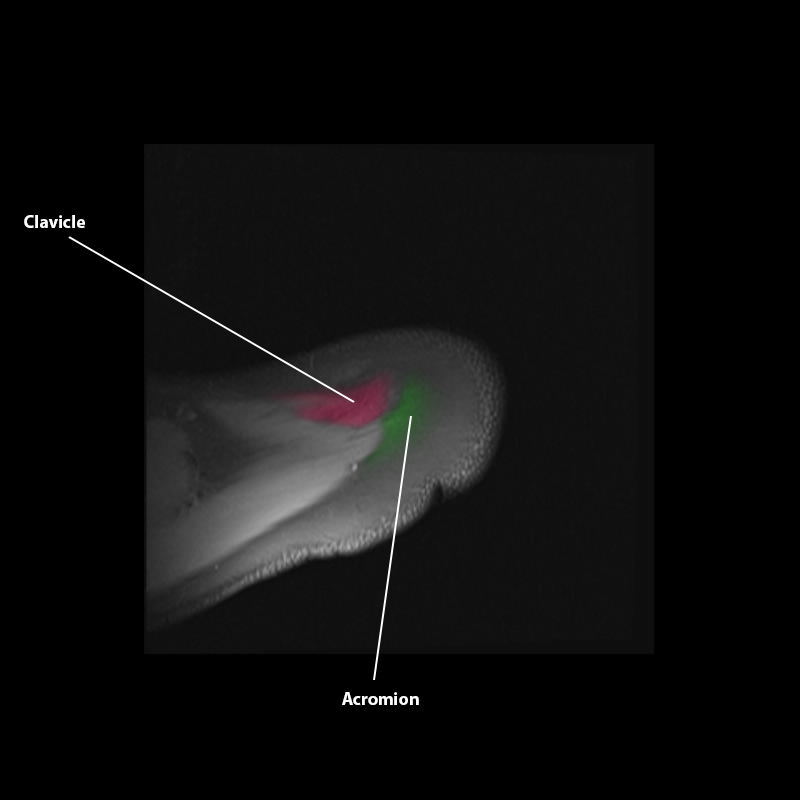

Shoulder MRI Anatomy